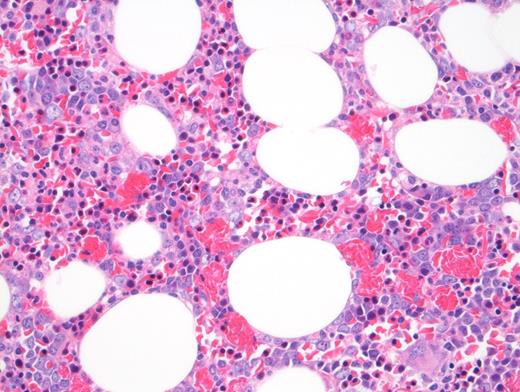

Peripheral blood showed abnormal red cell findings (Figure 1) with erythroblastosis (not shown). Aspirate showed trilineage hematopoiesis with erythroid predominance (Figure 2). Core biopsy showed hypercellular marrow (Figures 3 and 4) with focal areas of marrow damage (Figure 5). Hemoglobin high-performance liquid chromatography (HPLC) was performed (Figure 6).

The peripheral blood showed numerous target cells, burr cells, and microcytes, as well as partially sickled cells and blister-like cells. Core biopsy shows erythroid hyperplasia with large clusters of sickled cells (present in macrophages by CD68 stain; not shown).

The focal areas of bone marrow necrosis are the consequence of ischemic marrow damage caused by vascular obstruction by sickle cells. In a patient with sickle cell variant, multiorgan failure with altered mental status and focal bone marrow necrosis, the findings raise concern for bone marrow necrosis/fat embolism syndrome (BMN/FES).3 BMN/FES is more common in non– hemoglobin SS SCD variants such as hemoglobin SC.4 Brain MRI can show “starfield” on diffusion-weighted MRI in patients with severe neurologic impairment due to emboli.5,6 This patient did not undergo MRI after her decompensation.

The presence of blister cells and low G6PD activity (hemoglobin, 4.7 U/g; reference range, 8.8-13.4 U/ g) also argues for a component of oxidative damage causing ongoing hemolysis for this patient.While there is an erythroid expansion with left shift (and pronormoblasts present), there is trilineage hematopoiesis with maturation. Pronormoblasts are not greater than 30 percent of cellularity. Therefore, this case does not meet criteria for pure erythroid leukemia.8